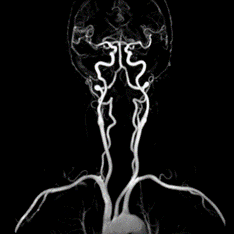

Siêu âm Dopplẻ hệ động mạch cảnh:

Sàng lọc tình trạng bệnh nhân tắc nghẽn hoặc hẹp động mạch cảnh.

Hình 7. Siêu âm Doppler hệ động mạch cảnh

Siêu âm Doppler mạch máu:

Khảo sát : ĐM cảnh – sống đoạn ngoài sọ, động tĩnh mạch chi trên, chi dưới, ĐM chủ bụng, các ĐM nuôi các tạng trong ổ bụng, ĐM thận, mạch máu não

Hình 8. Siêu âm Doppler mạch máu